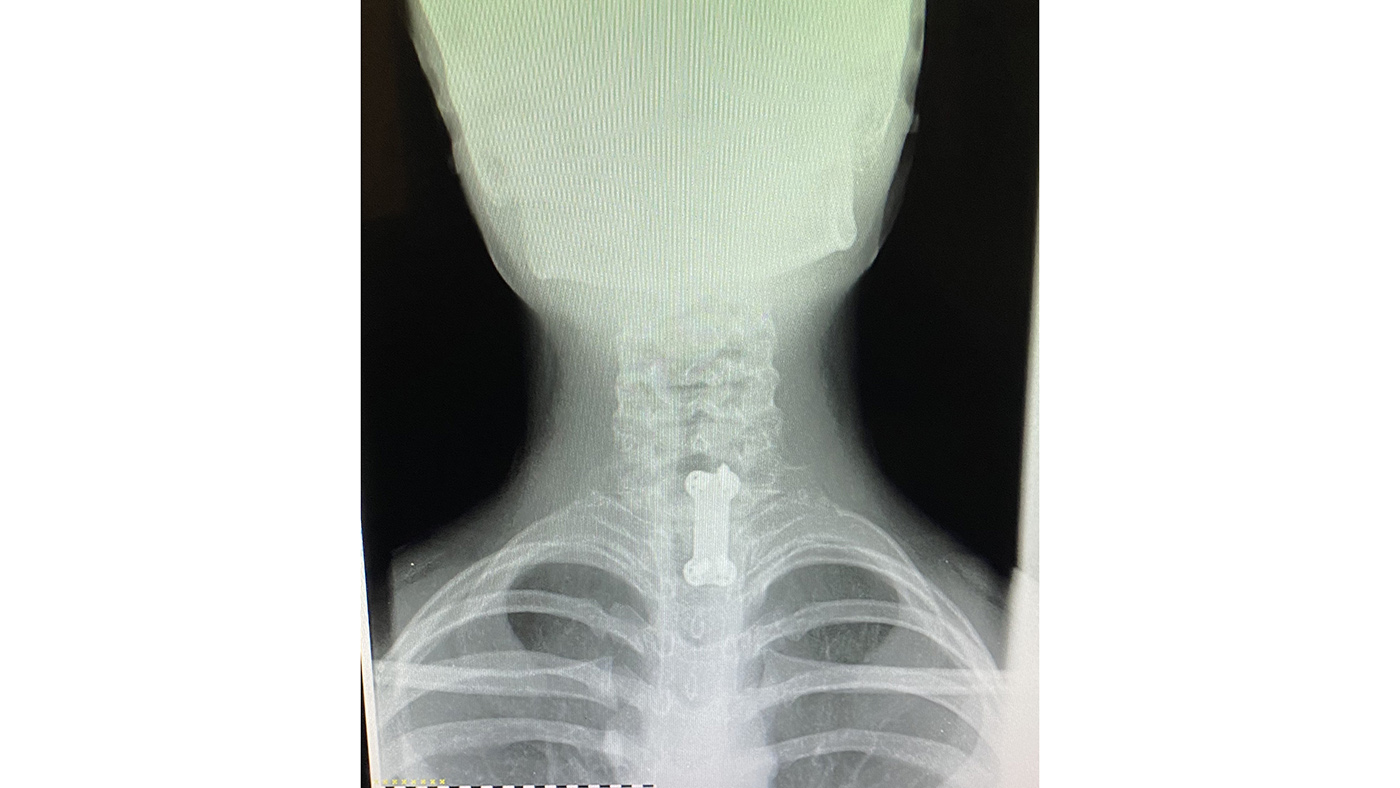

Lauren underwent the surgery that evening; Dr Noordeen and his team replaced the vertebra with a metal plate and four screws.